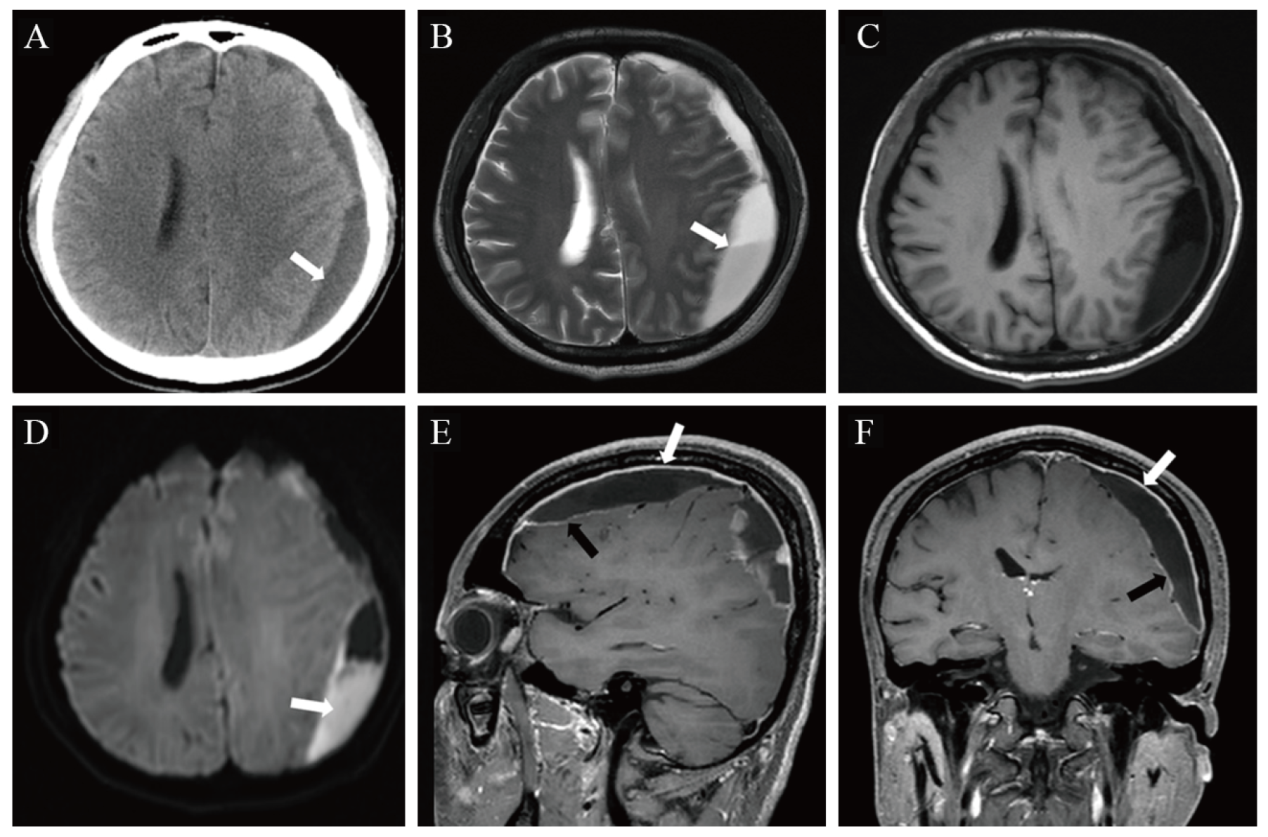

术后患者头痛缓解,术后12 d(2020年10月17日)脑脊液检查提示,蛋白246.6 mg/L(参考值范围80~430 mg/L),葡萄糖2.33 mmol/L(参考值范围2.2~3.9 mmol/L),氯化物132.4 mmol/L(参考值范围118~132 mmol/L),白细胞22×106/L(参考值范围0~8×106/L),球蛋白阳性。2020年10月20日复查颅脑MRI,提示左侧额顶部骨质内板下异常信号影范围明显缩小,额顶部硬脑膜及额顶叶软脑膜增厚,左侧顶叶片状低T1WI、高T2WI信号,提示脑实质水肿(图2A)。患者病情好转后出院。2021年2月5日,患者返院随访,未述不适,入院体格检查:患者神志清晰,反应正常,口腔未见白色伪膜,颈软无抵抗,生理反射存在,病理反射未引出。入院后实验室检查:超敏CRP 1.89 mg/L,血清淀粉样蛋白A 4.1 mg/L,IL-6 2.73 pg/L,ESR 16 mm/h,CD4+ T淋巴细胞计数242.75 /μL(参考值范围410~1 590 /μL),HIV RNA 检测阴性。复查颅脑CT示,左侧额顶部硬膜下低密度影完全消失,脑实质内未见异常密度(图2B)。

图2 一例艾滋病合并伤寒沙门菌感染致硬膜下脓肿患者随访影像学检查结果

注:A为颅脑MRI平扫T2FLAIR,检查时间为2020年10月20日,示左侧额顶部骨质内板下少许低信号影(黑箭头),左侧额顶部硬脑膜增厚(白箭头),左侧额顶叶软脑膜增厚;B为颅脑CT平扫,检查时间为2021年2月5日,左侧额顶部骨质内板下未见异常密度,脑实质内未见异常密度。